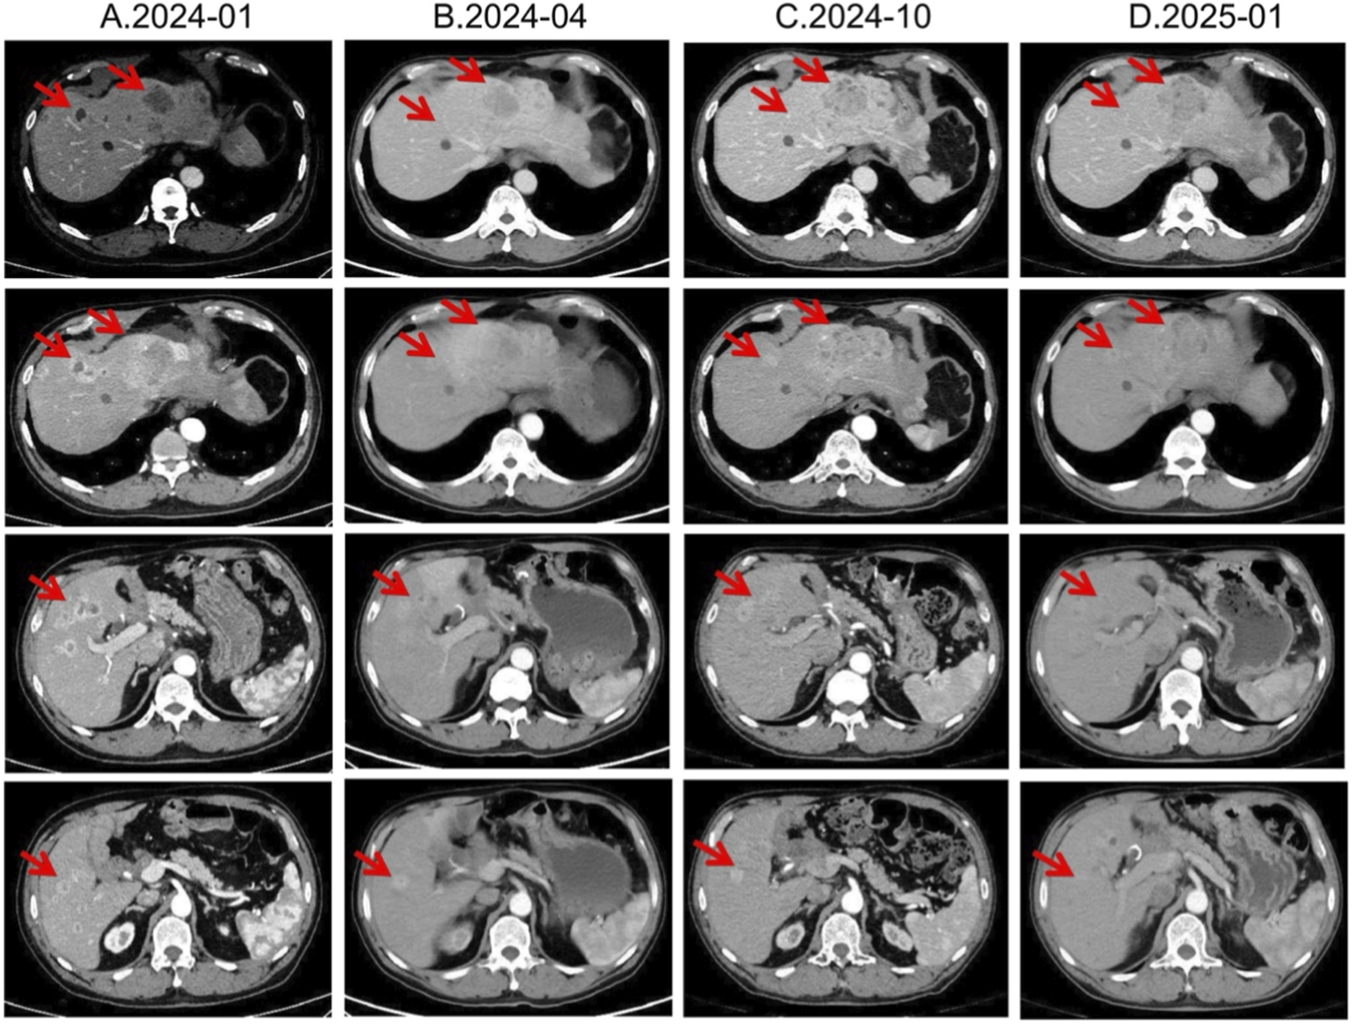

In January 2024, third-line treatment with everolimus 10 mg daily was initiated. Everolimus, an oral mTOR inhibitor, has been shown in RADIANT-3 and RADIANT-4 to significantly delay progression of advanced pNETs (Yao et al., 2016). In April and July 2024, CT scans demonstrated shrinkage of most hepatic lesions, with the treatment response assessed as a partial response (PR). However, owing to multiple small-intestinal ulcers at that time, the everolimus dose was reduced to 5 mg once daily in August 2024. Subsequent CT re-evaluations in October 2024 and January 2025 both showed SD (Figure 4).

FIGURE 4

Lesion changes in patients during third-line everolimus treatment. (A) 2024-01 CT shows: Multiple weakly enhanced nodules in the liver, the largest of which is approximately 4.3 cm × 2.8 cm in size. (B) 2024-04 CT shows: The liver lesions have decreased and shrunk compared with most of the previous lesions. Treatment response evaluation: PR. (C) 2024-10 CT shows: Multiple slightly low-density nodular mass shadows in the liver, especially in the left outer lobe of the liver. Enhanced scans show uneven enhancement. Treatment response evaluation: SD. (D) 2025-01 CT shows: Multiple slightly low-density nodular mass shadows in the liver, especially in the left outer lobe, and enhanced scans show heterogeneous enhancement. Treatment response evaluation: SD.